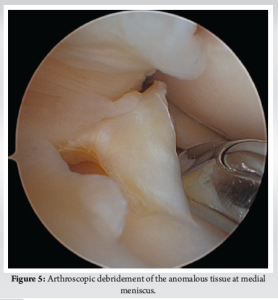

Diagnostic arthroscopy was performed secondary to pain, mechanical symptoms, and the diagnosis of a bucket-handle meniscus tear. Entry into the patellofemoral compartment revealed a large suprapatellar plica in contact with the lateral femoral condyle (Fig. 2). Within the medial compartment, diagnostic arthroscopy revealed the anomalous connection between the anterior and posterior horns (Fig. 3 and 4) and a radial tear at the posterior meniscus. The anomalous band was clearly a distinct structure from the medial meniscus with probing and became entrapped upon full extension of the knee. The band specifically ran from the posterior horn of the medial meniscus, superiorly, along the PCL, and ultimately attached to the anterior horn of the medial meniscus in an “O” shape. No chondral pathology was detected. A partial meniscectomy was performed to address the posterior radial tear located in the white–white zone, followed by debridement and removal of the anomalous attachment (Fig. 5 and 6).